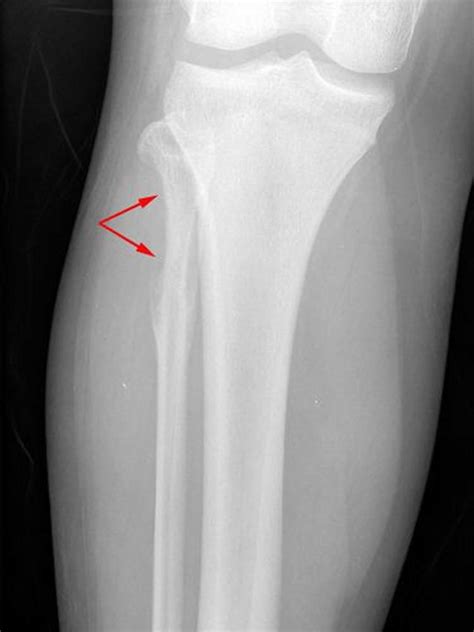

• Extent of Disease at Diagnosis: This is arguably the most significant factor. Patients with localized disease (cancer confined to the primary site) generally have a better prognosis than those with metastatic disease (cancer that has spread to distant sites like the lungs, bones, or bone marrow).

• Tumor Site: The location of the primary tumor matters. Tumors located in the pelvis or certain areas of the spine are often more challenging to treat effectively compared to those located in the arms or legs (extremities).

• Tumor Size: Smaller tumors are generally easier to treat and typically correlate with better outcomes compared to large, bulky tumors.